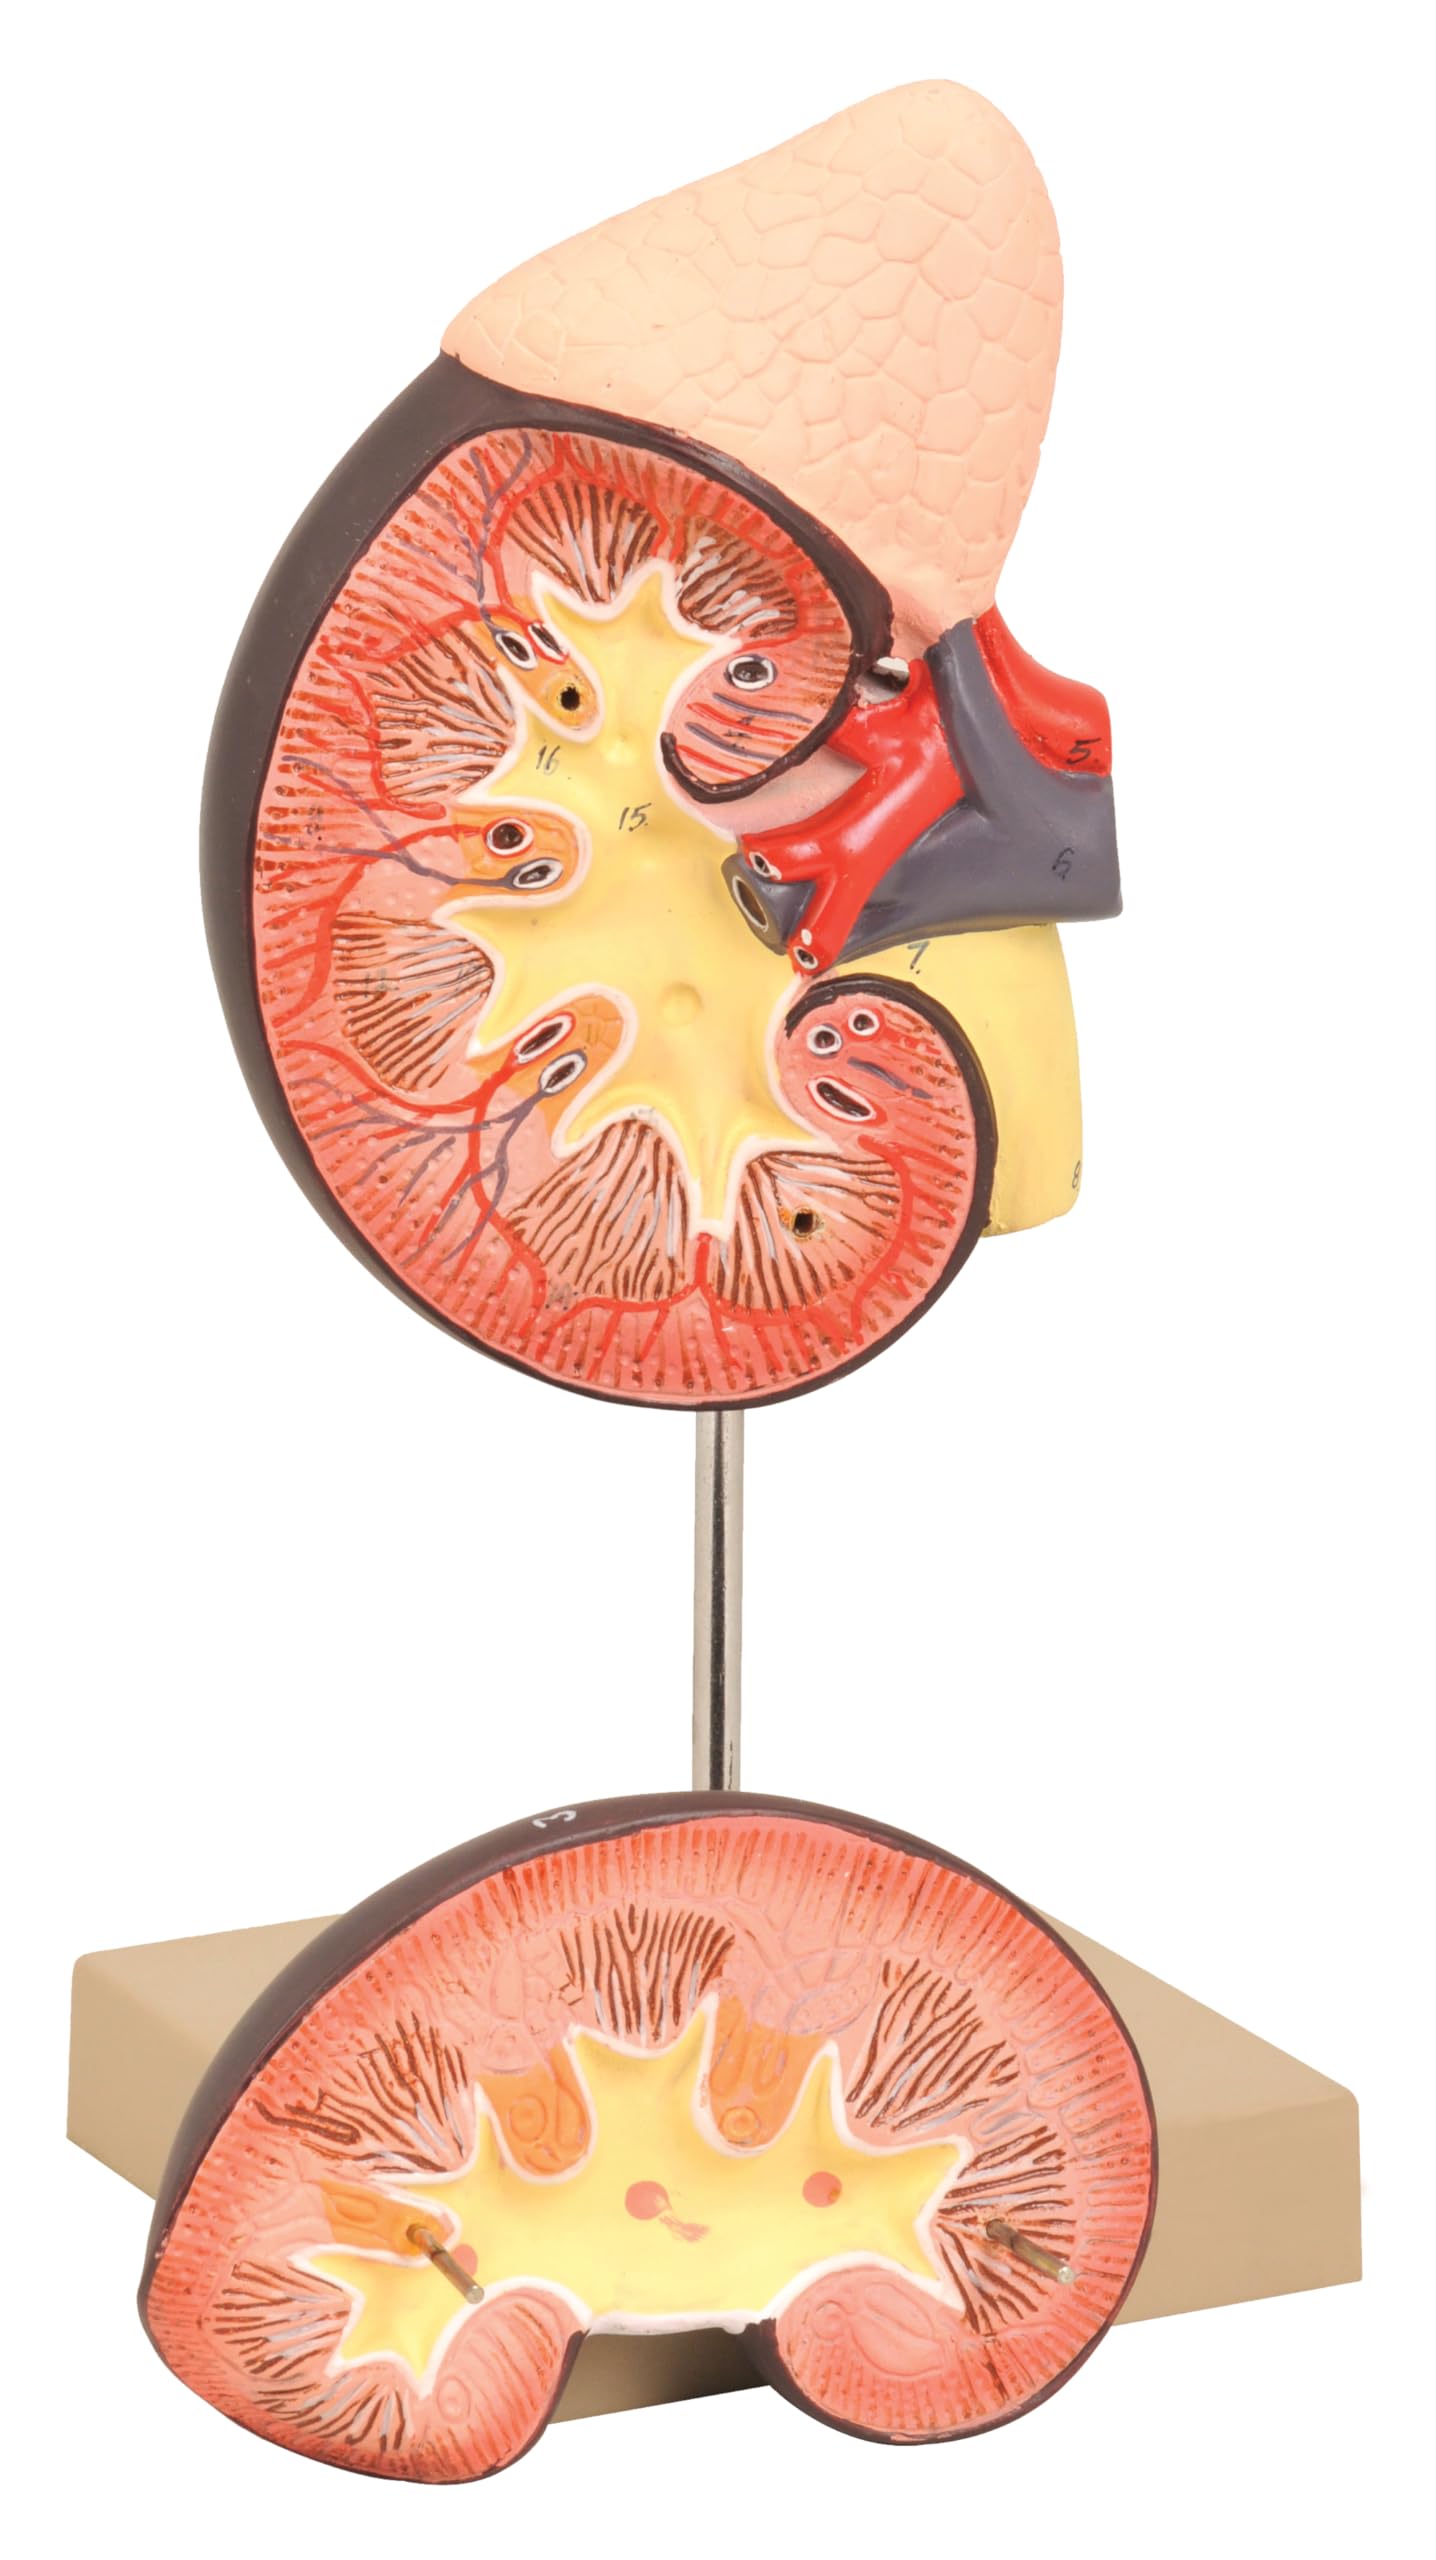

This is a life size replica model of a human kidney that hightlights the interworking of how the human kidney functions. Structures that are emphasized are the adrenal glands, the renal and adrenal vessels which help show how blood is filtered inside of the Bowman’s capsels. The removable front half of the model helps showcase the renal cortex, medulla, and the division of the renal artery down to the capillary level. The model is mounted on a solid base for decades of student use.

- LIFE-SIZE REPRESENTATION – Offers an accurate and tangible study tool for the human kidney and adrenal gland, perfect for students and healthcare professionals.

- DETAILED INTERNAL STRUCTURE – Removable front half allows a deeper look into the kidney’s cortex, medulla, vessels, and renal pelvis for an immersive learning experience.

- EDUCATIONAL ACCOMPANIMENT – Comes with a detailed key for easy identification of 16 distinct structures, boosting understanding and retention.

- ENHANCED VISIBILITY – Generous sizing ensures that even the smallest details are visible, making it easier to explain and study complex internal anatomy.

- STURDY & DETAILED MODEL – Constructed to withstand regular use in educational environments, this model delivers durability along with anatomically correct features.